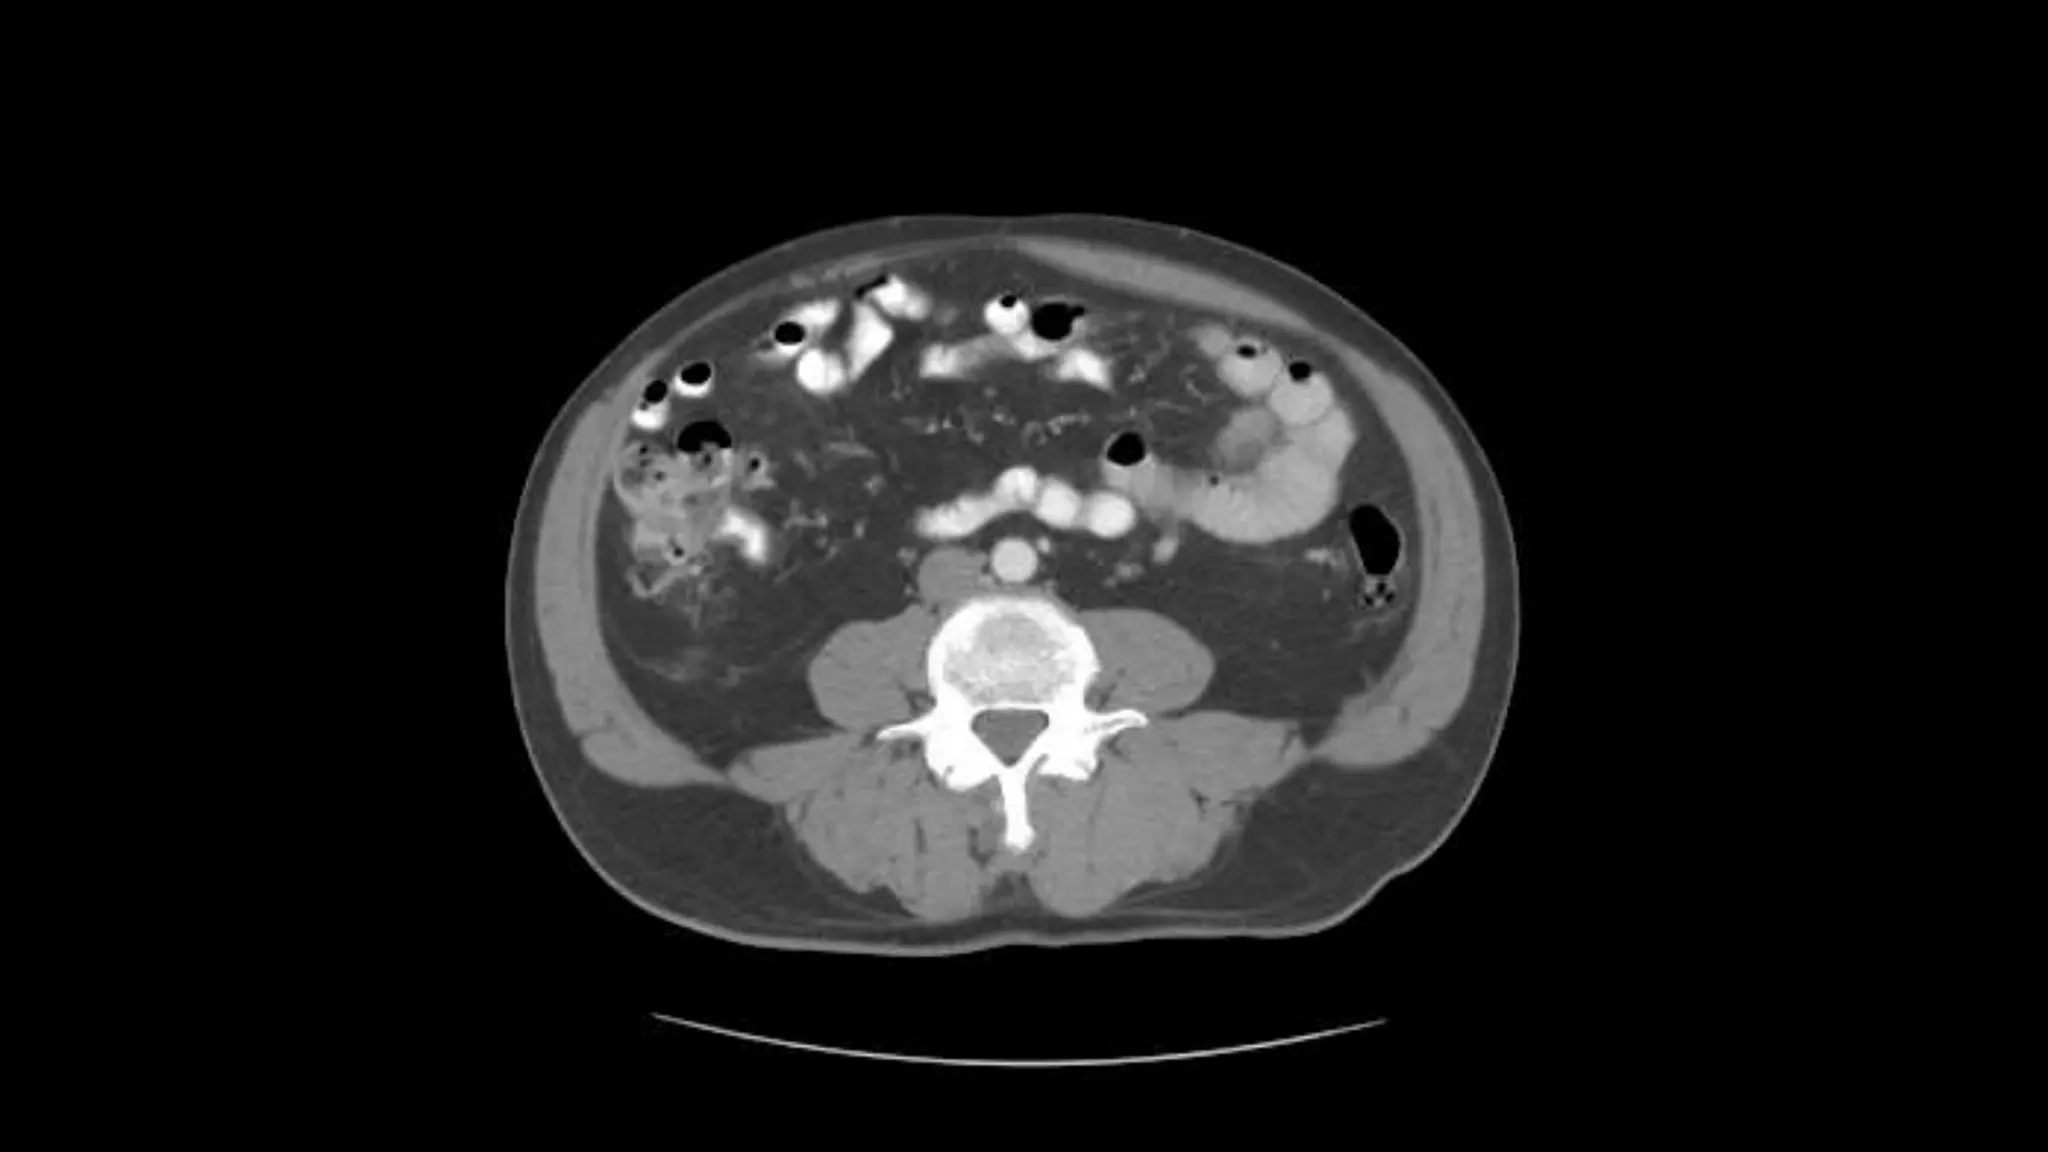

Note inferior mesentericartery emerging from aorta Inferior mesenteric vein extends cephalad to join smv.

Aorta bifurcates intocommon illiac arteries Appendix is noted coiling in Rt. Lower quadrant Note air in lumen on adjacent scans Psoas muscles